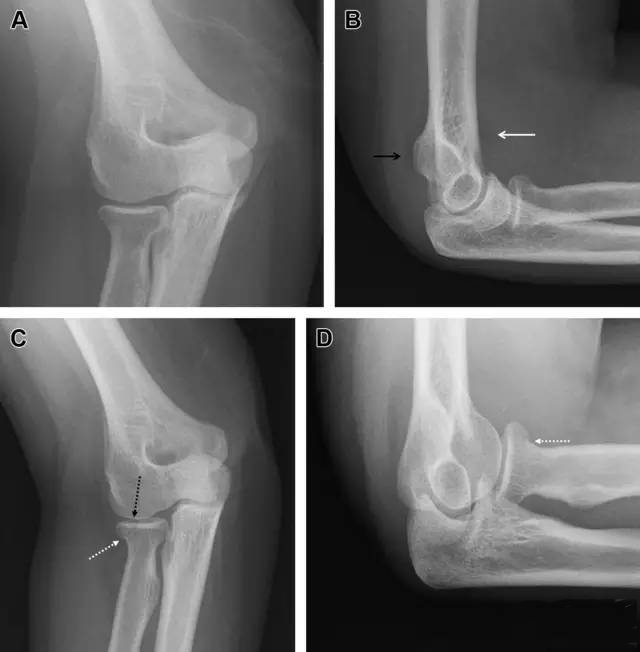

多发生于摔倒时,手掌撑地,受到轴向、外翻应力所致。常规的前后位片容易漏诊,常需加拍内斜位、外斜位、桡骨头-肱骨小头位片。后脂肪垫可见(位于鹰嘴窝内,一般不可见)和/或前脂肪垫抬高常提示骨性损伤。

图2 桡骨头骨折。前后位(A)和侧位(B)片示后脂肪垫抬高(黑色箭头),前脂肪垫抬高(白色箭头),呈「帆船征」,其它表现正常;外斜位(C)和桡骨头–肱骨小头位(D)示桡骨头关节内骨折线(虚线黑箭头)累及桡骨颈(虚线白箭头)